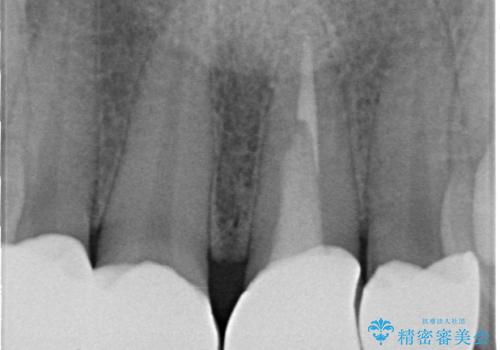

- 前歯の見た目を良くしたいとのことで来院された患者様です。今までに保険のプラスチック(コンポジットレジン)で虫歯の治療をしており経年的な劣化により着色が目立つようになっていました。また歯と歯の隣り合っているところに段差もあり虫歯になっていたり、詰め物も外れていたため前歯4本のオールセラミッククラウンによる治療を行うこととなりました。

拡大鏡視野下で保険のプラスチック(コンポジットレジン)、虫歯、左上1の被せものを除去し、オールセラミッククラウンに適した形にしました。

歯と歯茎の間に圧排糸と言われる糸を入れてシリコーン印象材にて型どりをしました。